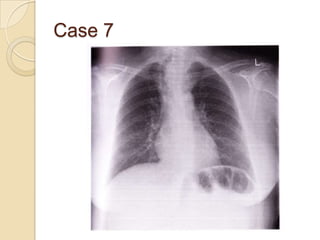

Case 7

   Mass lesion in

mediastinum

?enlarged thyroid

gland

◦ Tracheal deviation

caused by mass

◦ Long volume, ribs

and diaphragms are

normal

Case 7  Mass lesion in mediastinum ?enlarged thyroid gland ◦ Tracheal deviation caused by mass ◦ Long volume, ribs and diaphragms are normal